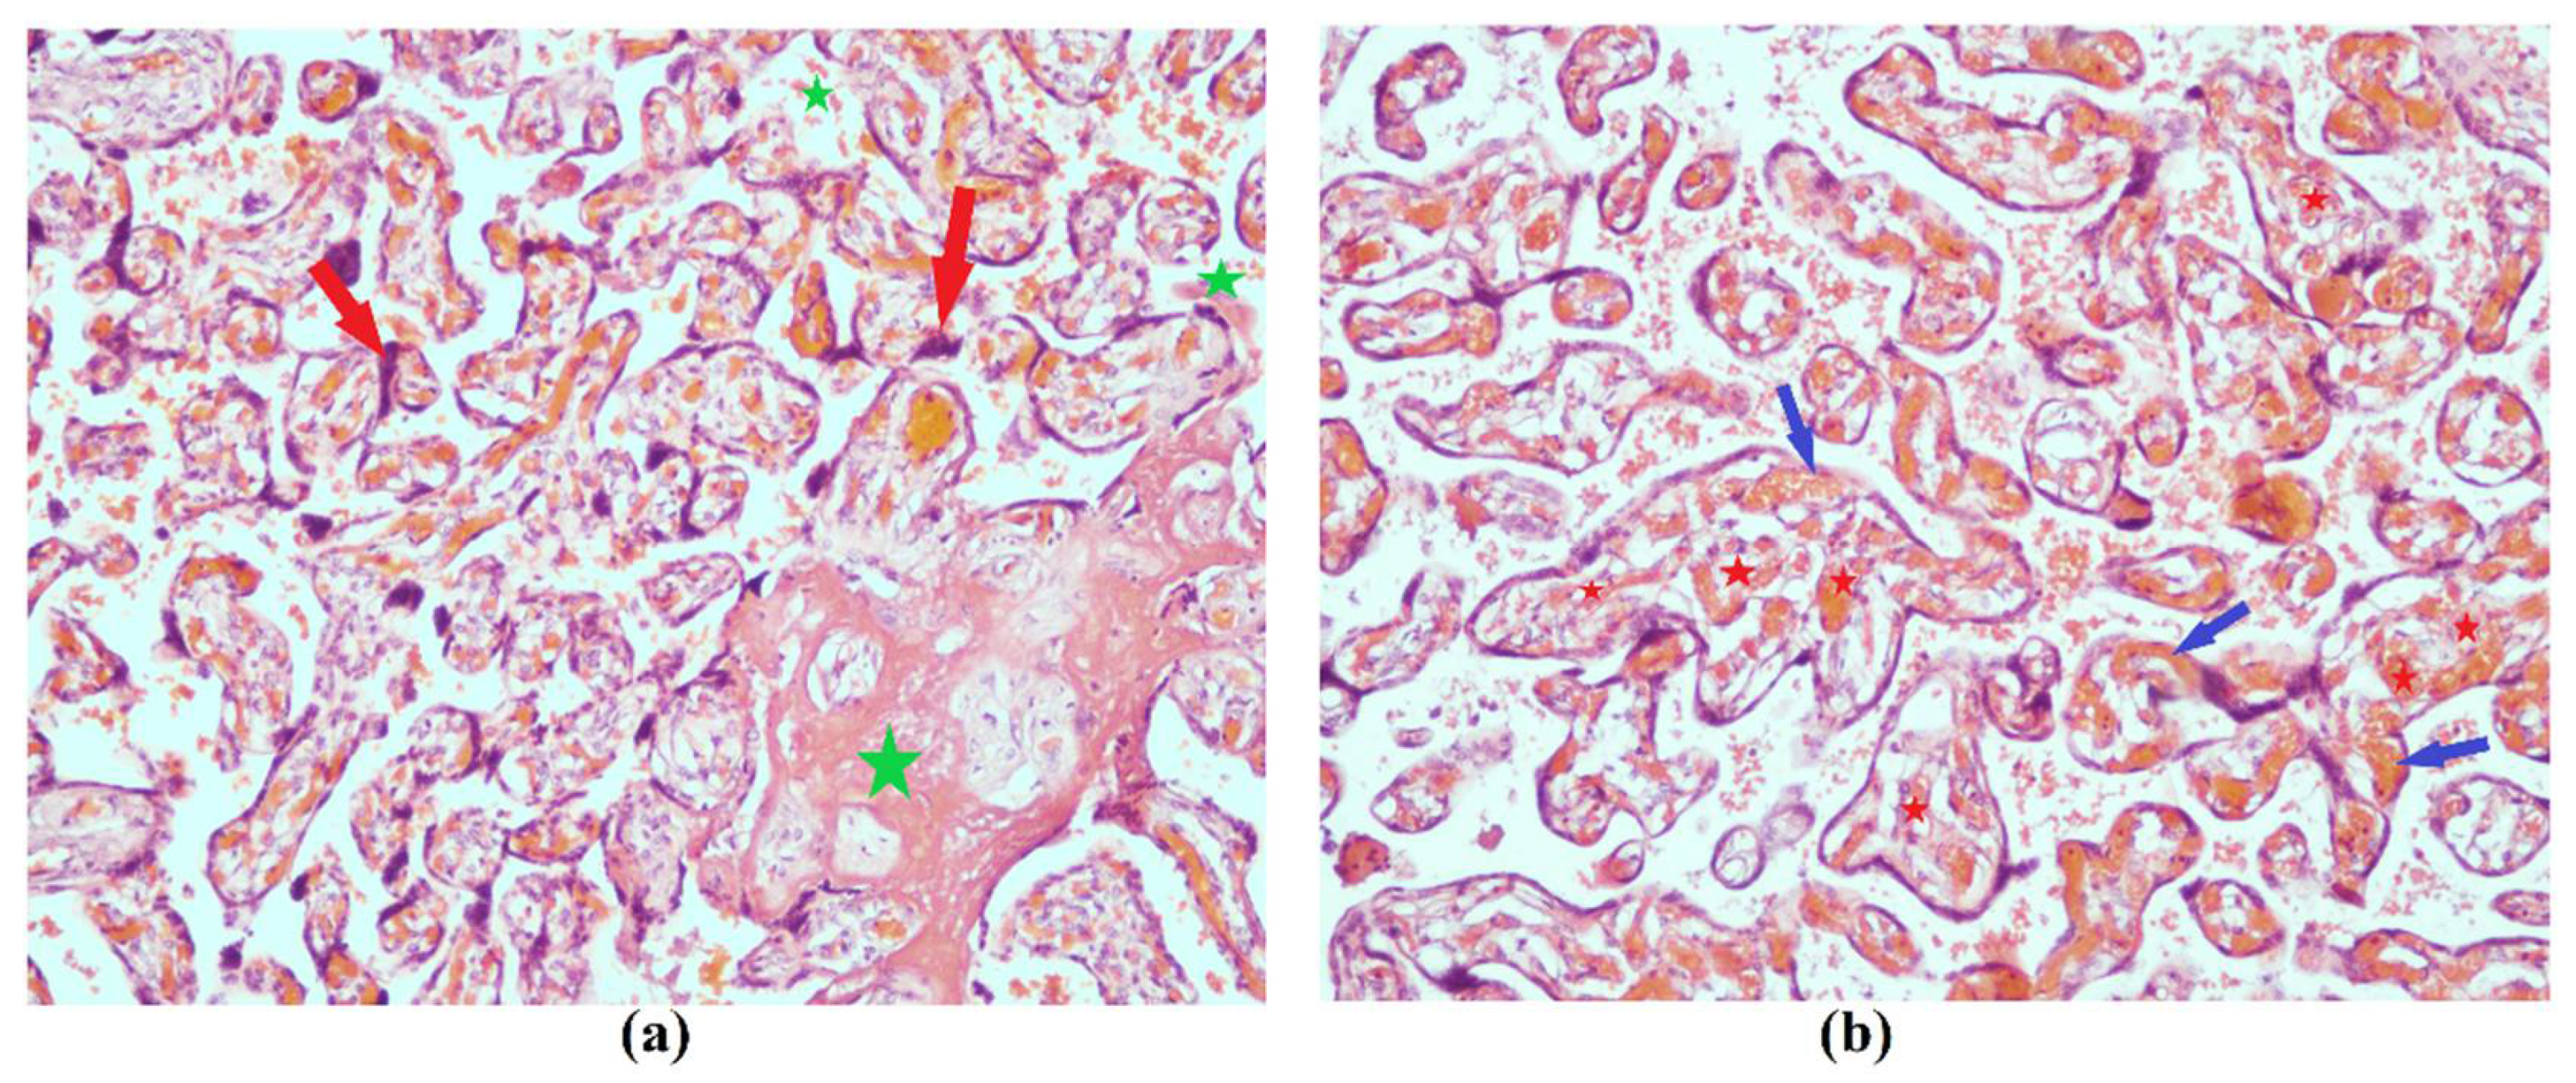

3.1.2. Data of the Instrumental Methods of Examination